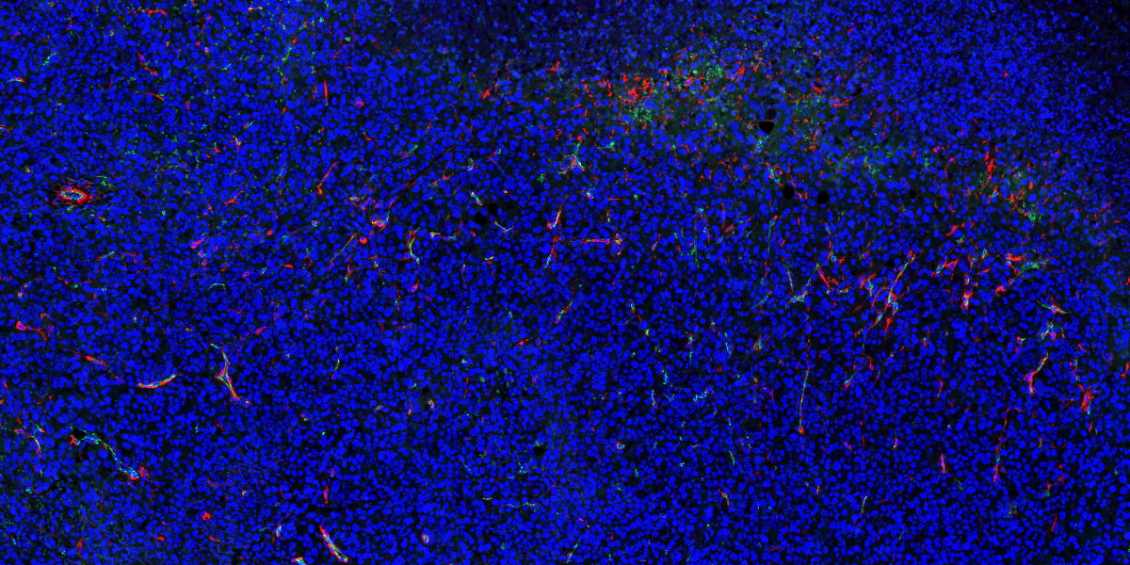

云南石蜡切片免疫荧光不可避免会产生自发荧光。

1.取材的时候灌注取材,把红细胞冲洗干净;

2.脱蜡必须彻底,封闭、洗涤等过程也需充分;

3.抗体在使用前最好先离心处理并尽量从上方吸取,抗体的浓度过高也会产生自发荧光,所以可以预实验摸清最合适的抗体浓度再进行正式实验;

4.如若自发荧光很强,严重影响染色效果,亦可采用自发荧光去除剂进行去除。